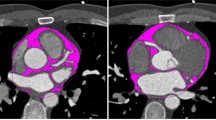

CTEAT, defined as the total amount of adipose tissue between the surface of the heart and the visceral layer of the pericardium, was measured by volumetry on short-axis slices with a thickness of 0.75 mm, ranging from the level of the pulmonary bifurcation to the apex and within a threshold range of -190 to -30 Hounsfield units (HU) to determine the total volume of tissue [17]. The adipose tissue around the coronary artery is part of the EAT and was defined as the attenuation coefficient of the fat tissue voxels within a distance from the coronary arterial wall equal to the corresponding vessel diameter. The attenuation coefficient was calculated separately for the right coronary artery (RCA), left anterior descending artery (LAD), and left circumflex artery (LCX) using the coronary artery analysis module [18].

The cardiac mass was determined using the syngo.via cardiac analysis module, which automatically traces the endocardial and epicardial borders to generate the volume of the heart. The myocardial volumes were converted to left ventricle mass (M) by assuming a constant tissue density of myocardium (1.05 g/cc). CTV/M was calculated by dividing the luminal volume of the coronary artery by the myocardial mass of the heart [9, 19]. The luminal volume of the coronary artery was extracted by a deep learning calculation method on the workstation. In this study, the right coronary artery was selected for coronary lumen volume analysis given its simplicity and thick diameter in the Chinese population.

Except for CTV/M (26.2% [IQR, 24.4; 27.8] vs. 22.0% [IQR, 21.0; 24.0], P < 0.01), the CCTA-derived parameters in the healthy groups were significantly lower (P < 0.05) than those in the non-ICHF group (Table 1). In non-ICHF, the volume of adipose tissue around the proximal LAD (-79.8 HU [IQR, -78.2; -81.3]) was higher than that around the RCA (-68.9 HU [IQR, -65.3; -73.1]) and LCX (-73.3 HU [IQR, -67.1; -75.4]) (Table 1, Fig. 2).